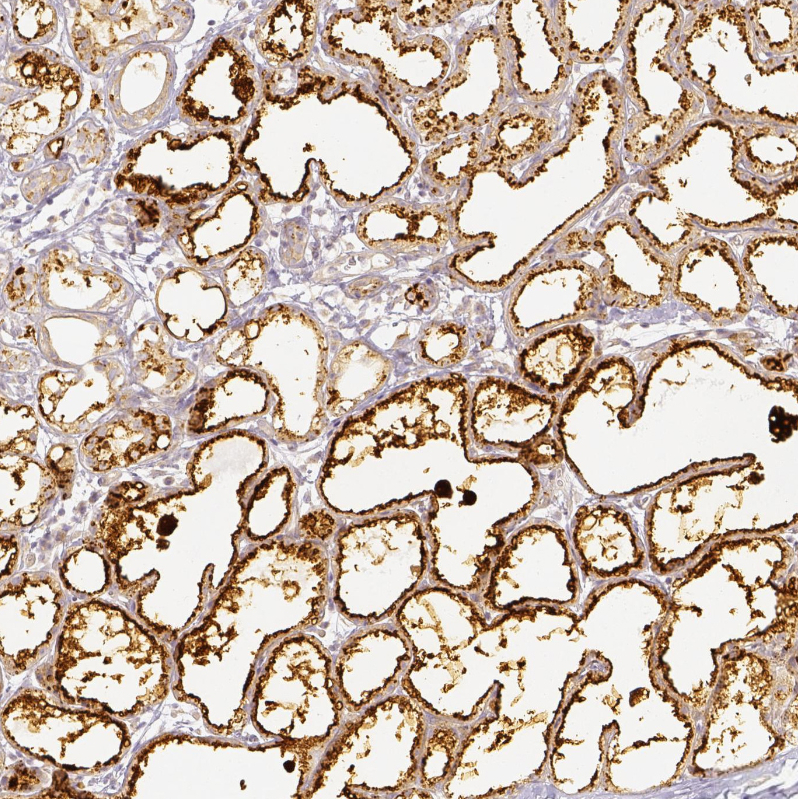

Immunohistochemical staining of human lactating breast shows strong positivity in glandular cells.